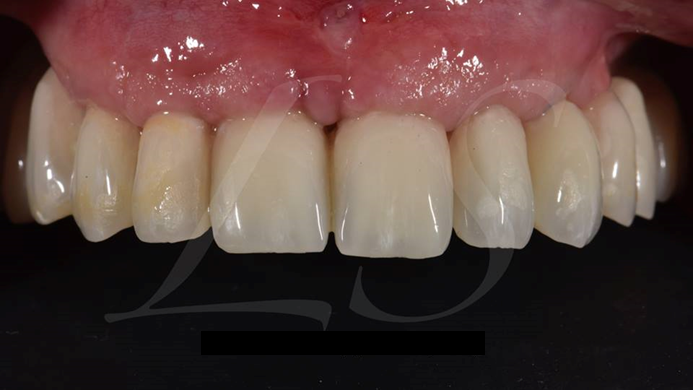

Clinical case: Full-arch implant treatment with immediate loading & extraction implantation

- Courtesy of Dr. Laurent Sers, France -

AnyRidge, R2GATE, guided surgery, Dr. Laurent Sers, immediate loading, maxilla

AnyRidge implant system, R2GATE, Digital prosthesis

“Patient’s smile was recovered on the day of surgery

with reliable & highly-aesthetic results using AnyRidge & R2GATE. ”